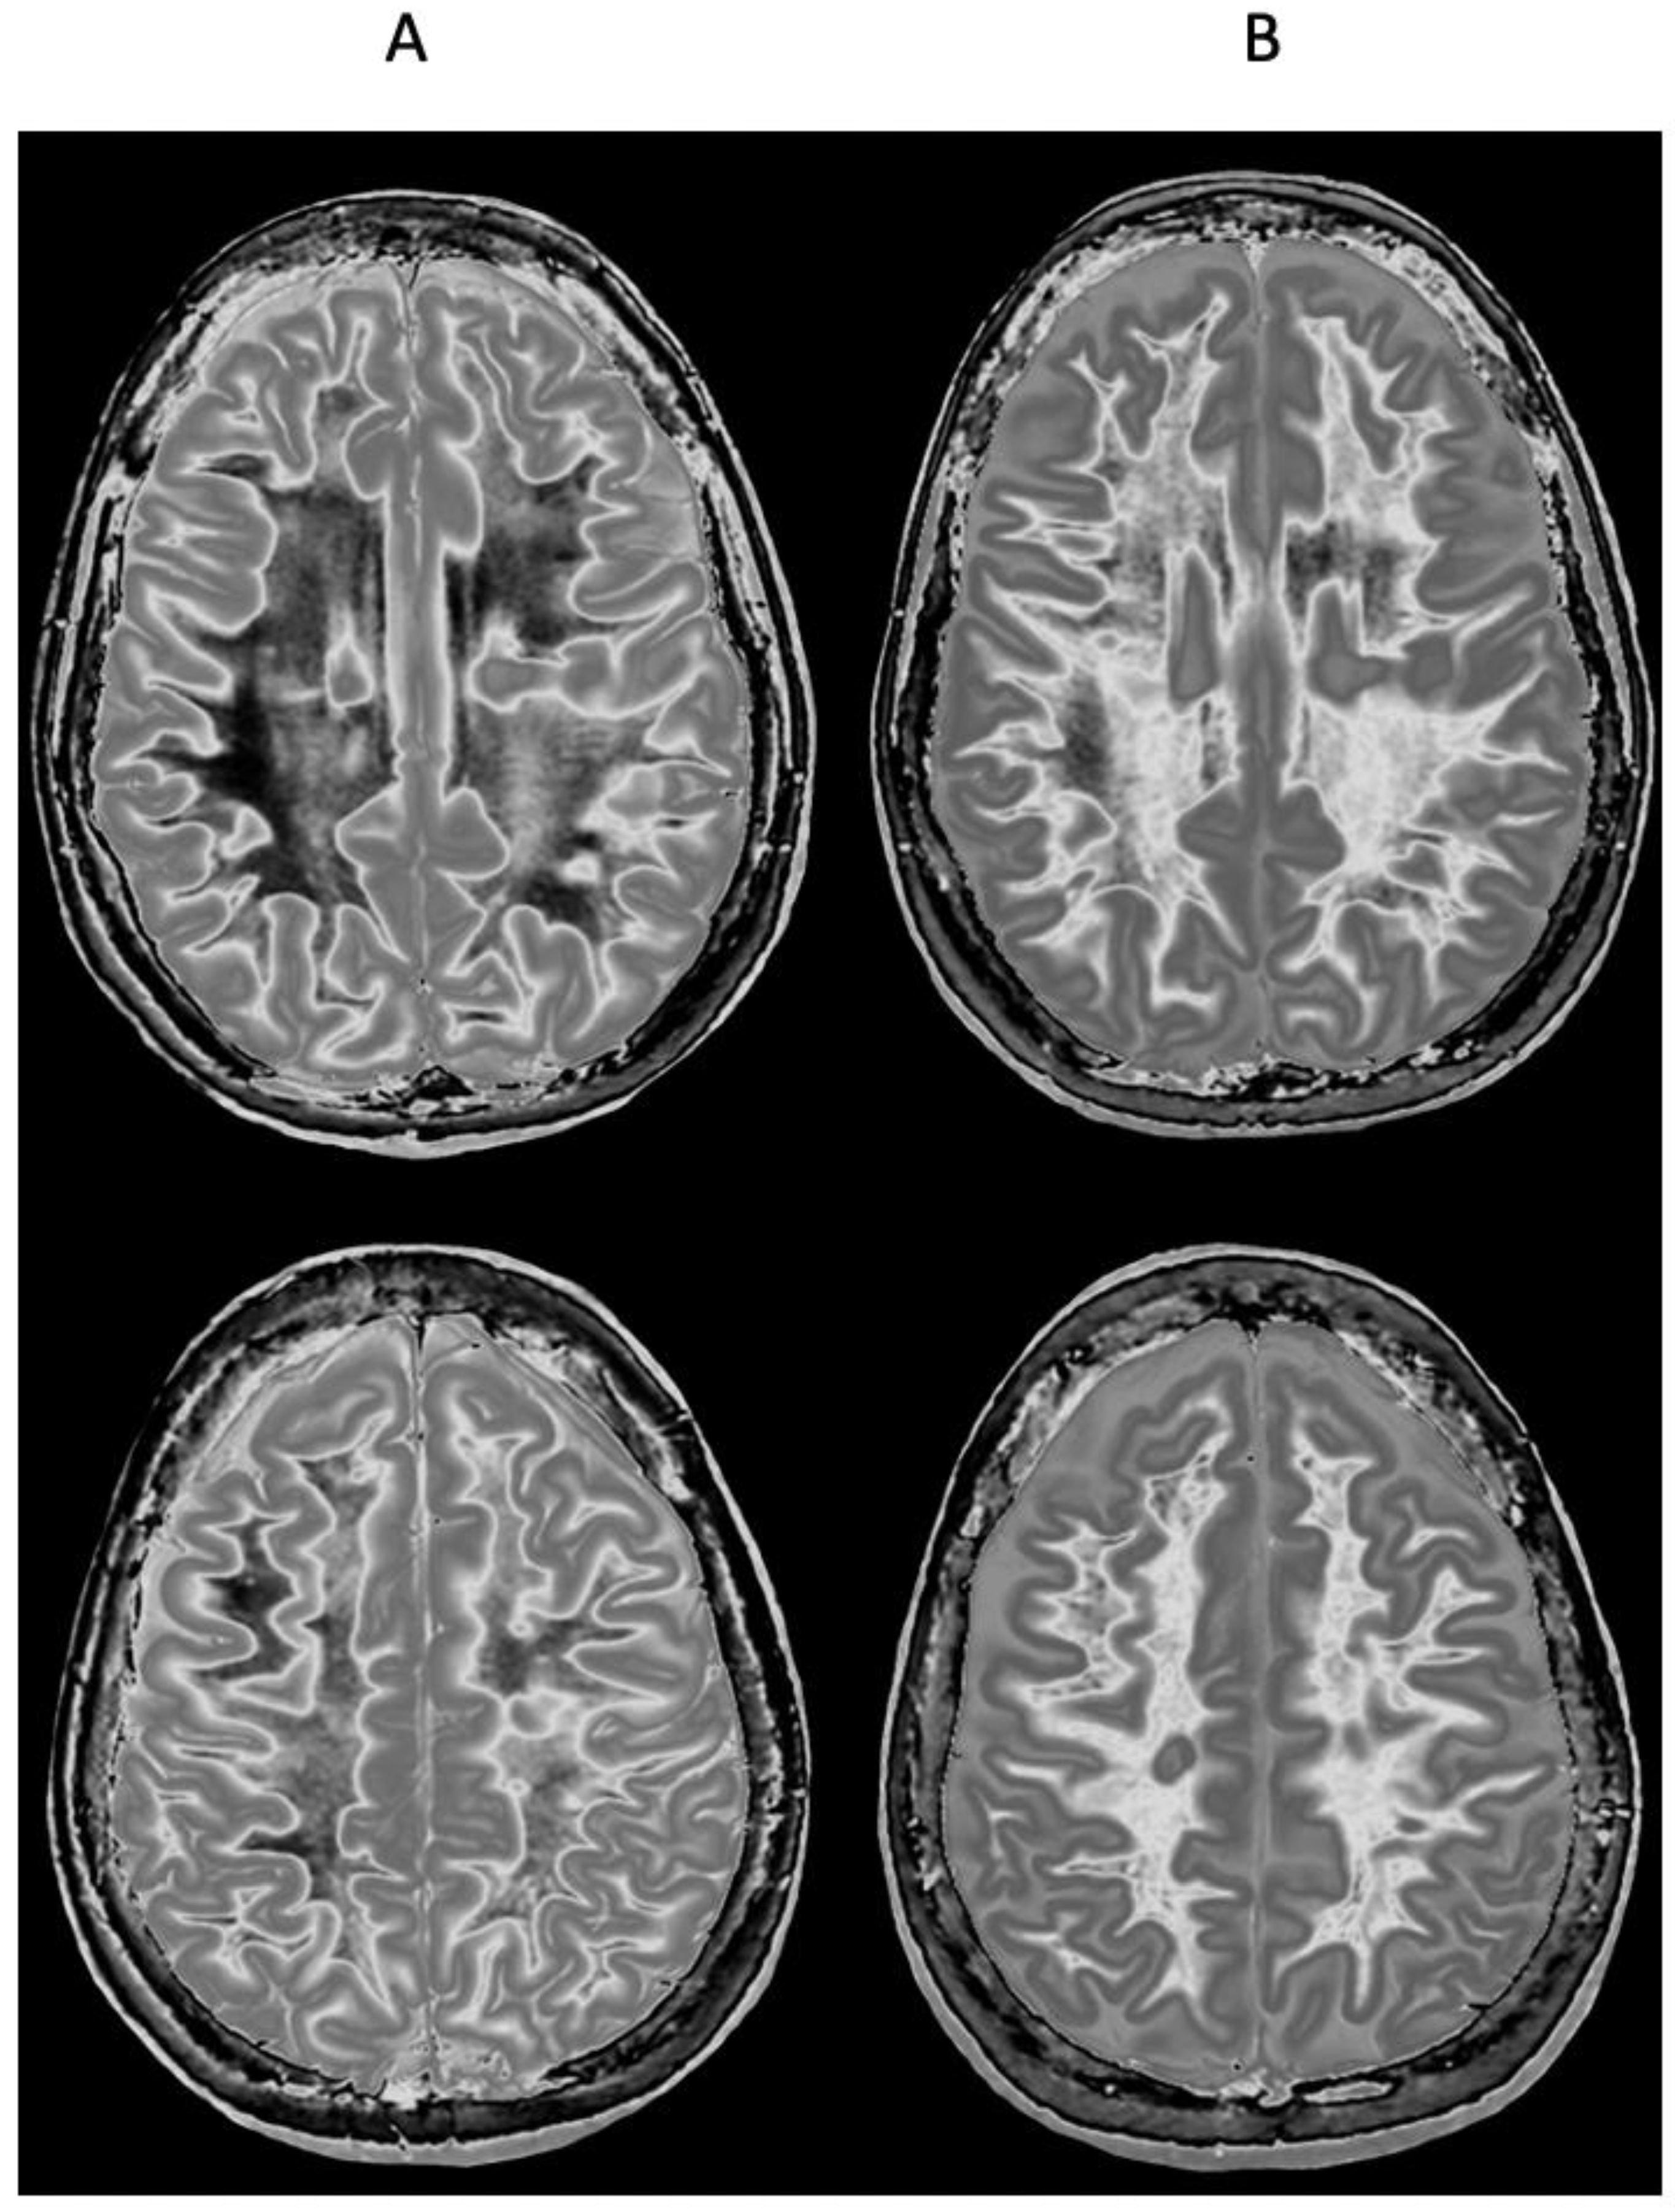

4. Illustrative Cases

5.2.1. Whiteout Sign

5.2.2. Grayout Signs

5.4. Other Sequences Using Two IR Sequences